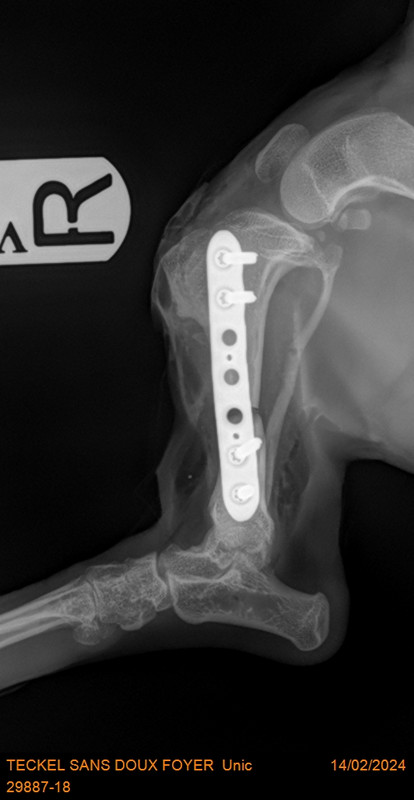

voici les radios avec les plaques qui ont été mises pour redresser

[Image: 29887-18-TECKEL-SANS-DOUX-FOYER-Unic-13381.jpg]

impressionnant !

C est impressionnant..il va se sentir mieux pour marcher [Image: coeur%20joyeux.gif] [Image: coeur%20joyeux.gif] [Image: calin-1844.gif] [Image: calin-1844.gif] [Image: des%20bisous.gif] [Image: des%20bisous.gif]